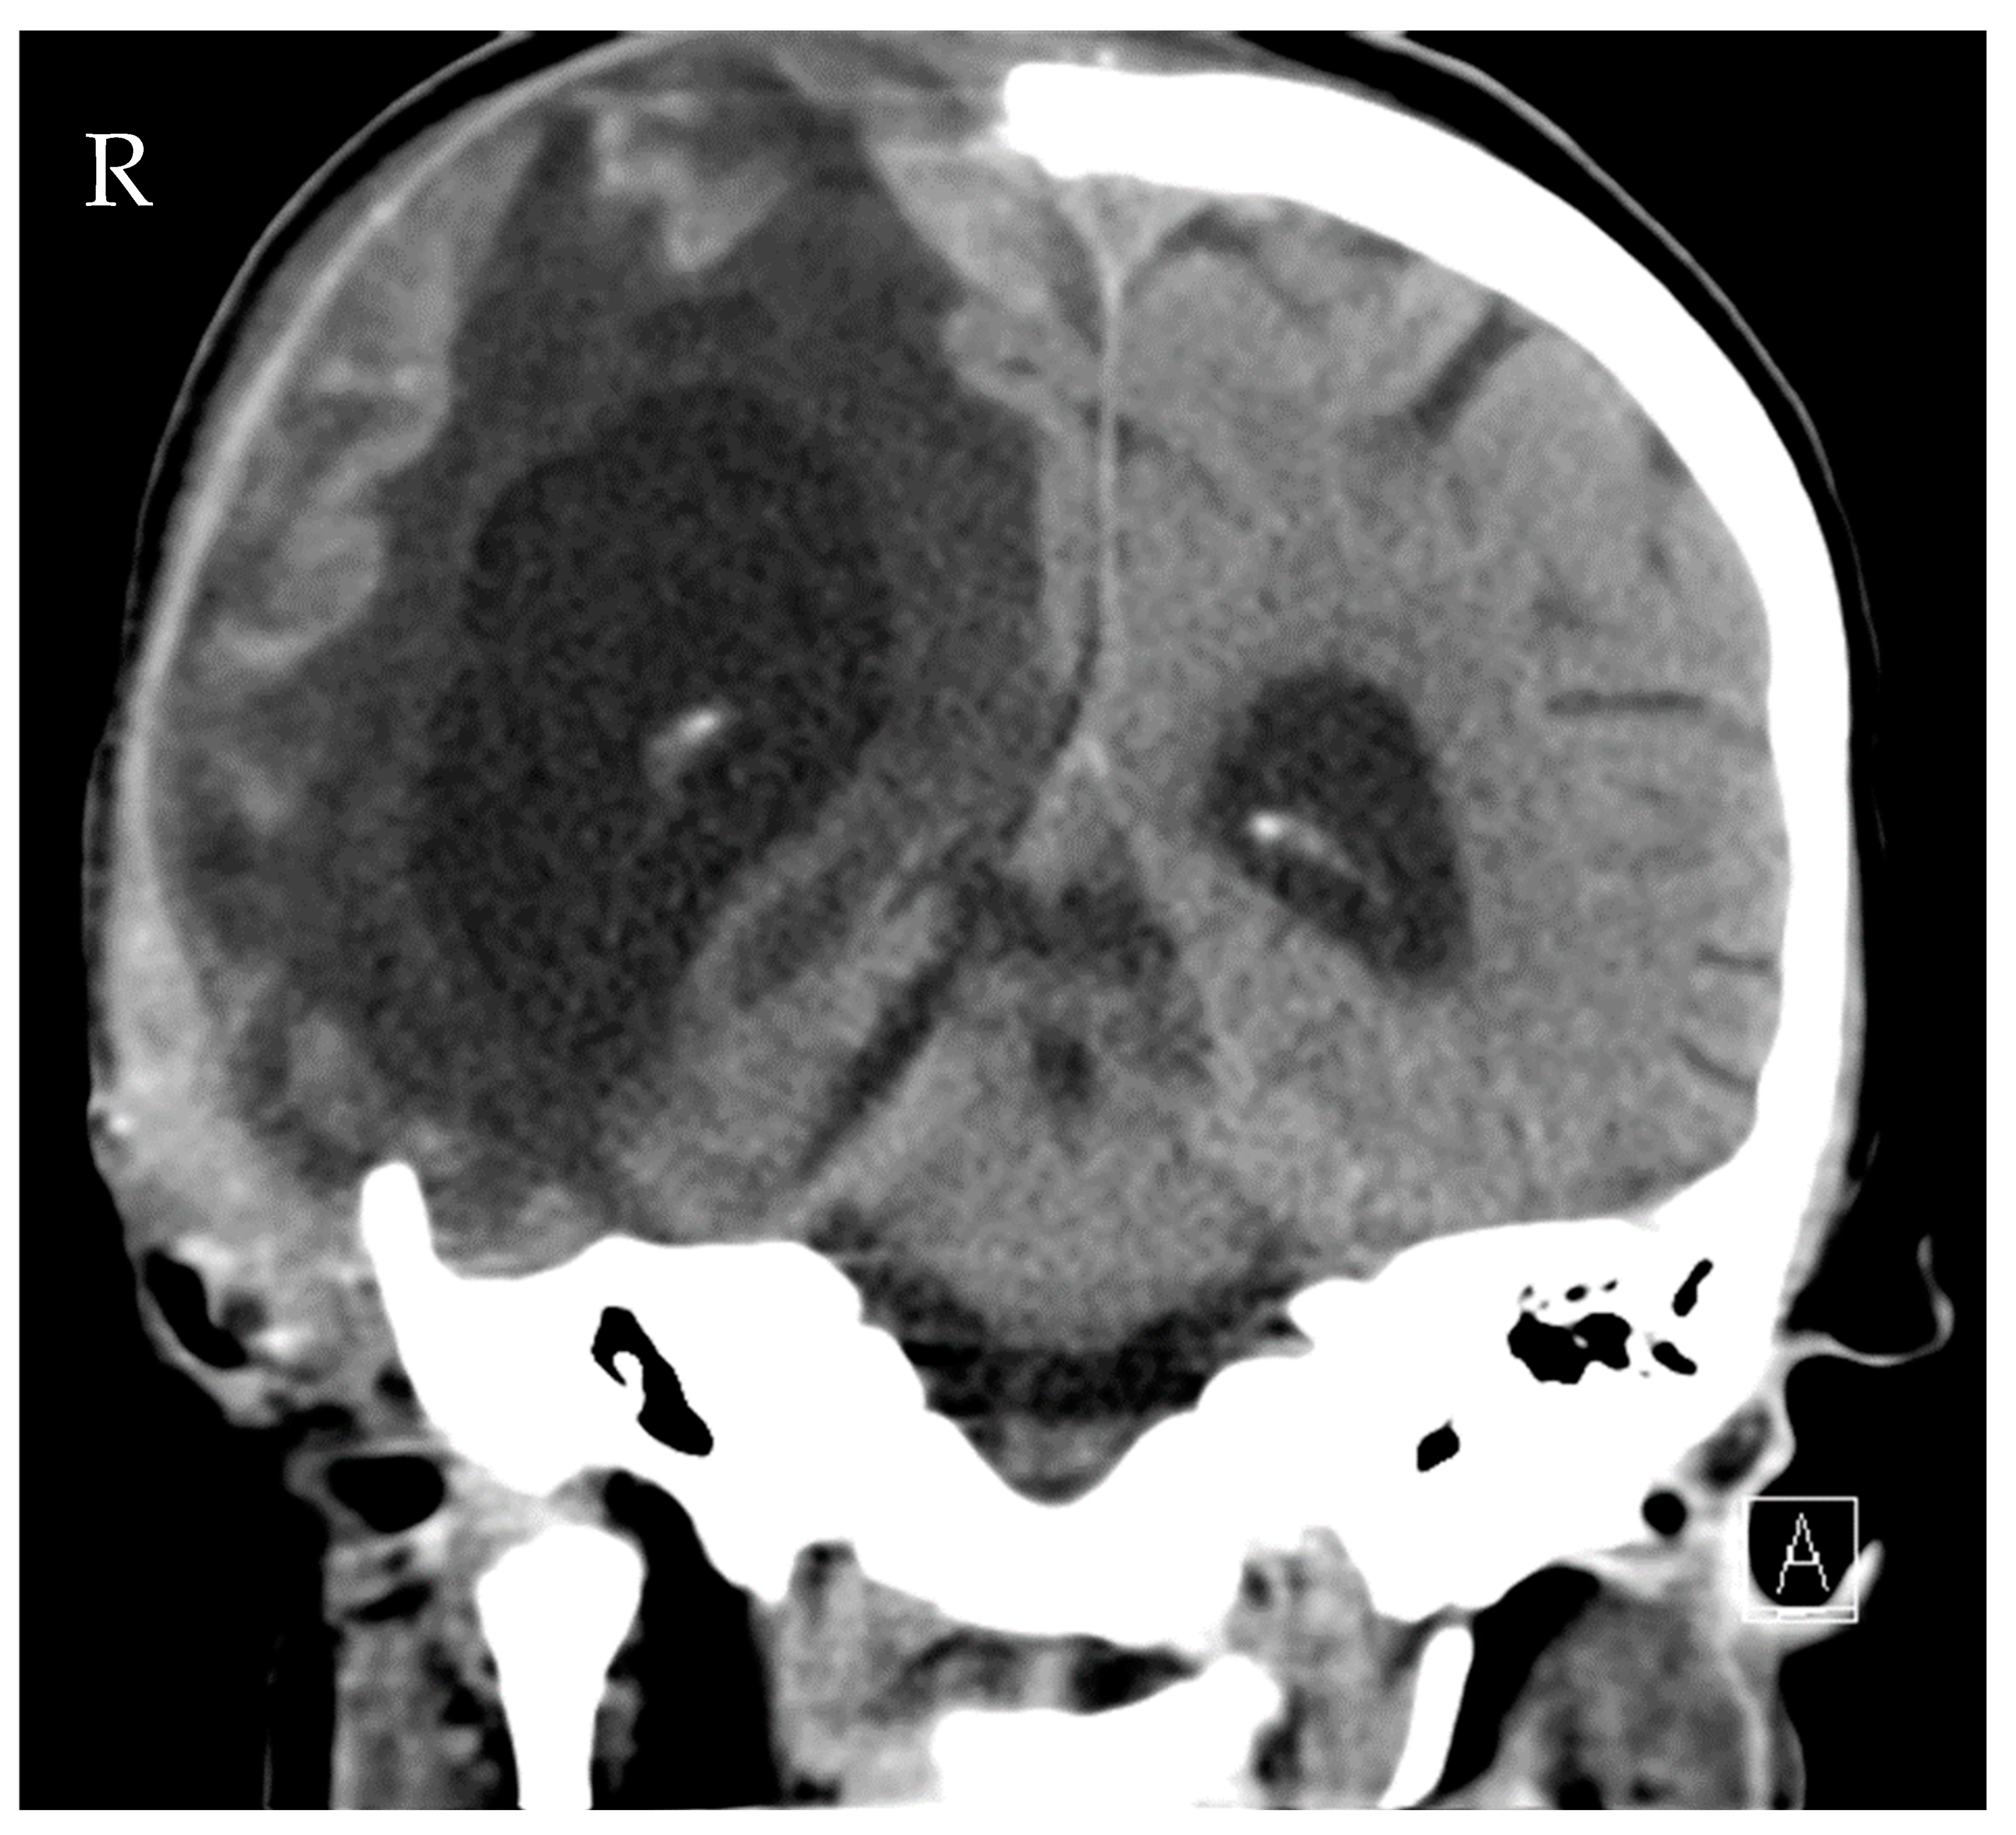

Source control was also conducted: the initial LD was removed, and a new EVD was inserted due to ongoing high ICP (combination of hydrocephalus e vacuo and malresorptivus). See Figure 4 for the corresponding computed tomography. Therapy success was measured through microbiology cure: The cerebrospinal fluid (CSF) culture became negative after 7 days of C/T treatment, and the CSF cell count decreased. The neurological status improved rapidly as a sign of clinical therapy success, and the CRP and leucocytes decreased rapidly, as shown in Figure 3. Another 10 days later, the definitive treatment of hydrocephalus could be obtained with a ventriculoatrial catheter. By the time of hospital discharge, the patient was awake and able to move all four extremities.

Figure 4.

Computed tomography of the head showing distinctive hydrocephalus with pronounced enlargement of the ventricular system (malresorptivus and e-vacuo components).